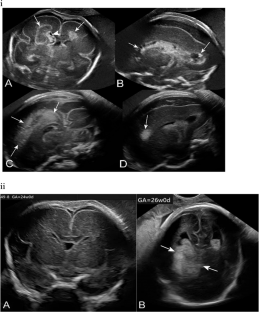

Genetic alterations in COL4A2 are less common than those of COL4A1 and their fetal phenotype has not been described to date. We describe a three-generation family with an intragenic deletion in COL4A2 associated with a prenatal diagnosis of recurrent fetal intracerebral hemorrhage (ICH), and a myriad of cerebrovascular manifestations. Exome sequencing, co-segregation analysis, and imaging studies were conducted on eight family members including two fetuses with antenatal ICH. Histopathological evaluation was performed on the terminated fetuses. An intragenic heterozygous pathogenic in-frame deletion; COL4A2, c.4151_4168del, (p.Thr1384_Gly1389del) was identified in both fetuses, their father with hemiplegic cerebral palsy (CP), as well as other family members. Postmortem histopathological examination identified microscopic foci of heterotopias and polymicrogyria. The variant segregated in affected individuals demonstrating varying degrees of penetrance and a wide phenotypic spectrum including periventricular venous hemorrhagic infarction causing hemiplegic CP, polymicrogyria, leukoencephalopathy, and lacunar stroke. We present radiographic, pathological, and genetic evidence of prenatal ICH and show, for what we believe to be the first time, a human pathological proof of polymicrogyria and heterotopias in association with a COL4A2 disease-causing variant, while illustrating the variable phenotype and partial penetrance of this disease. We highlight the importance of genetic analysis in fetal ICH and hemiplegic CP.